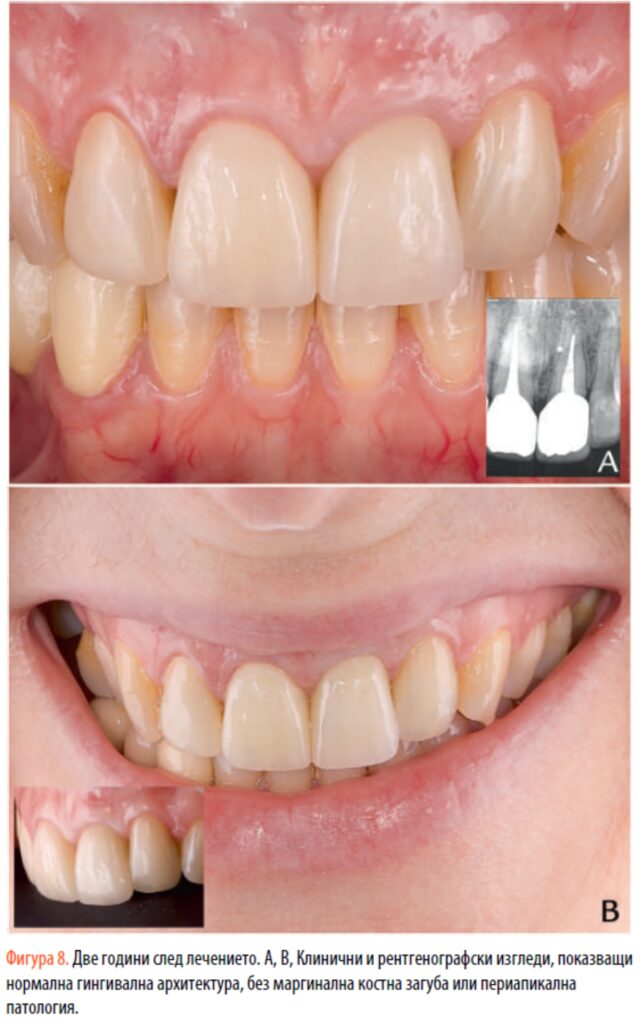

Пациентът беше извикван на 4 седмици и след това на 6, 12 и 24 месеца. Две години след лечението възстановителният ръб остава стабилен по отношение на гингивалния ръб (фиг. 8). Пациентът е асимптоматичен и периапикалната рентгенография не показва признаци на резорбция или ендодонтска недостатъчност.